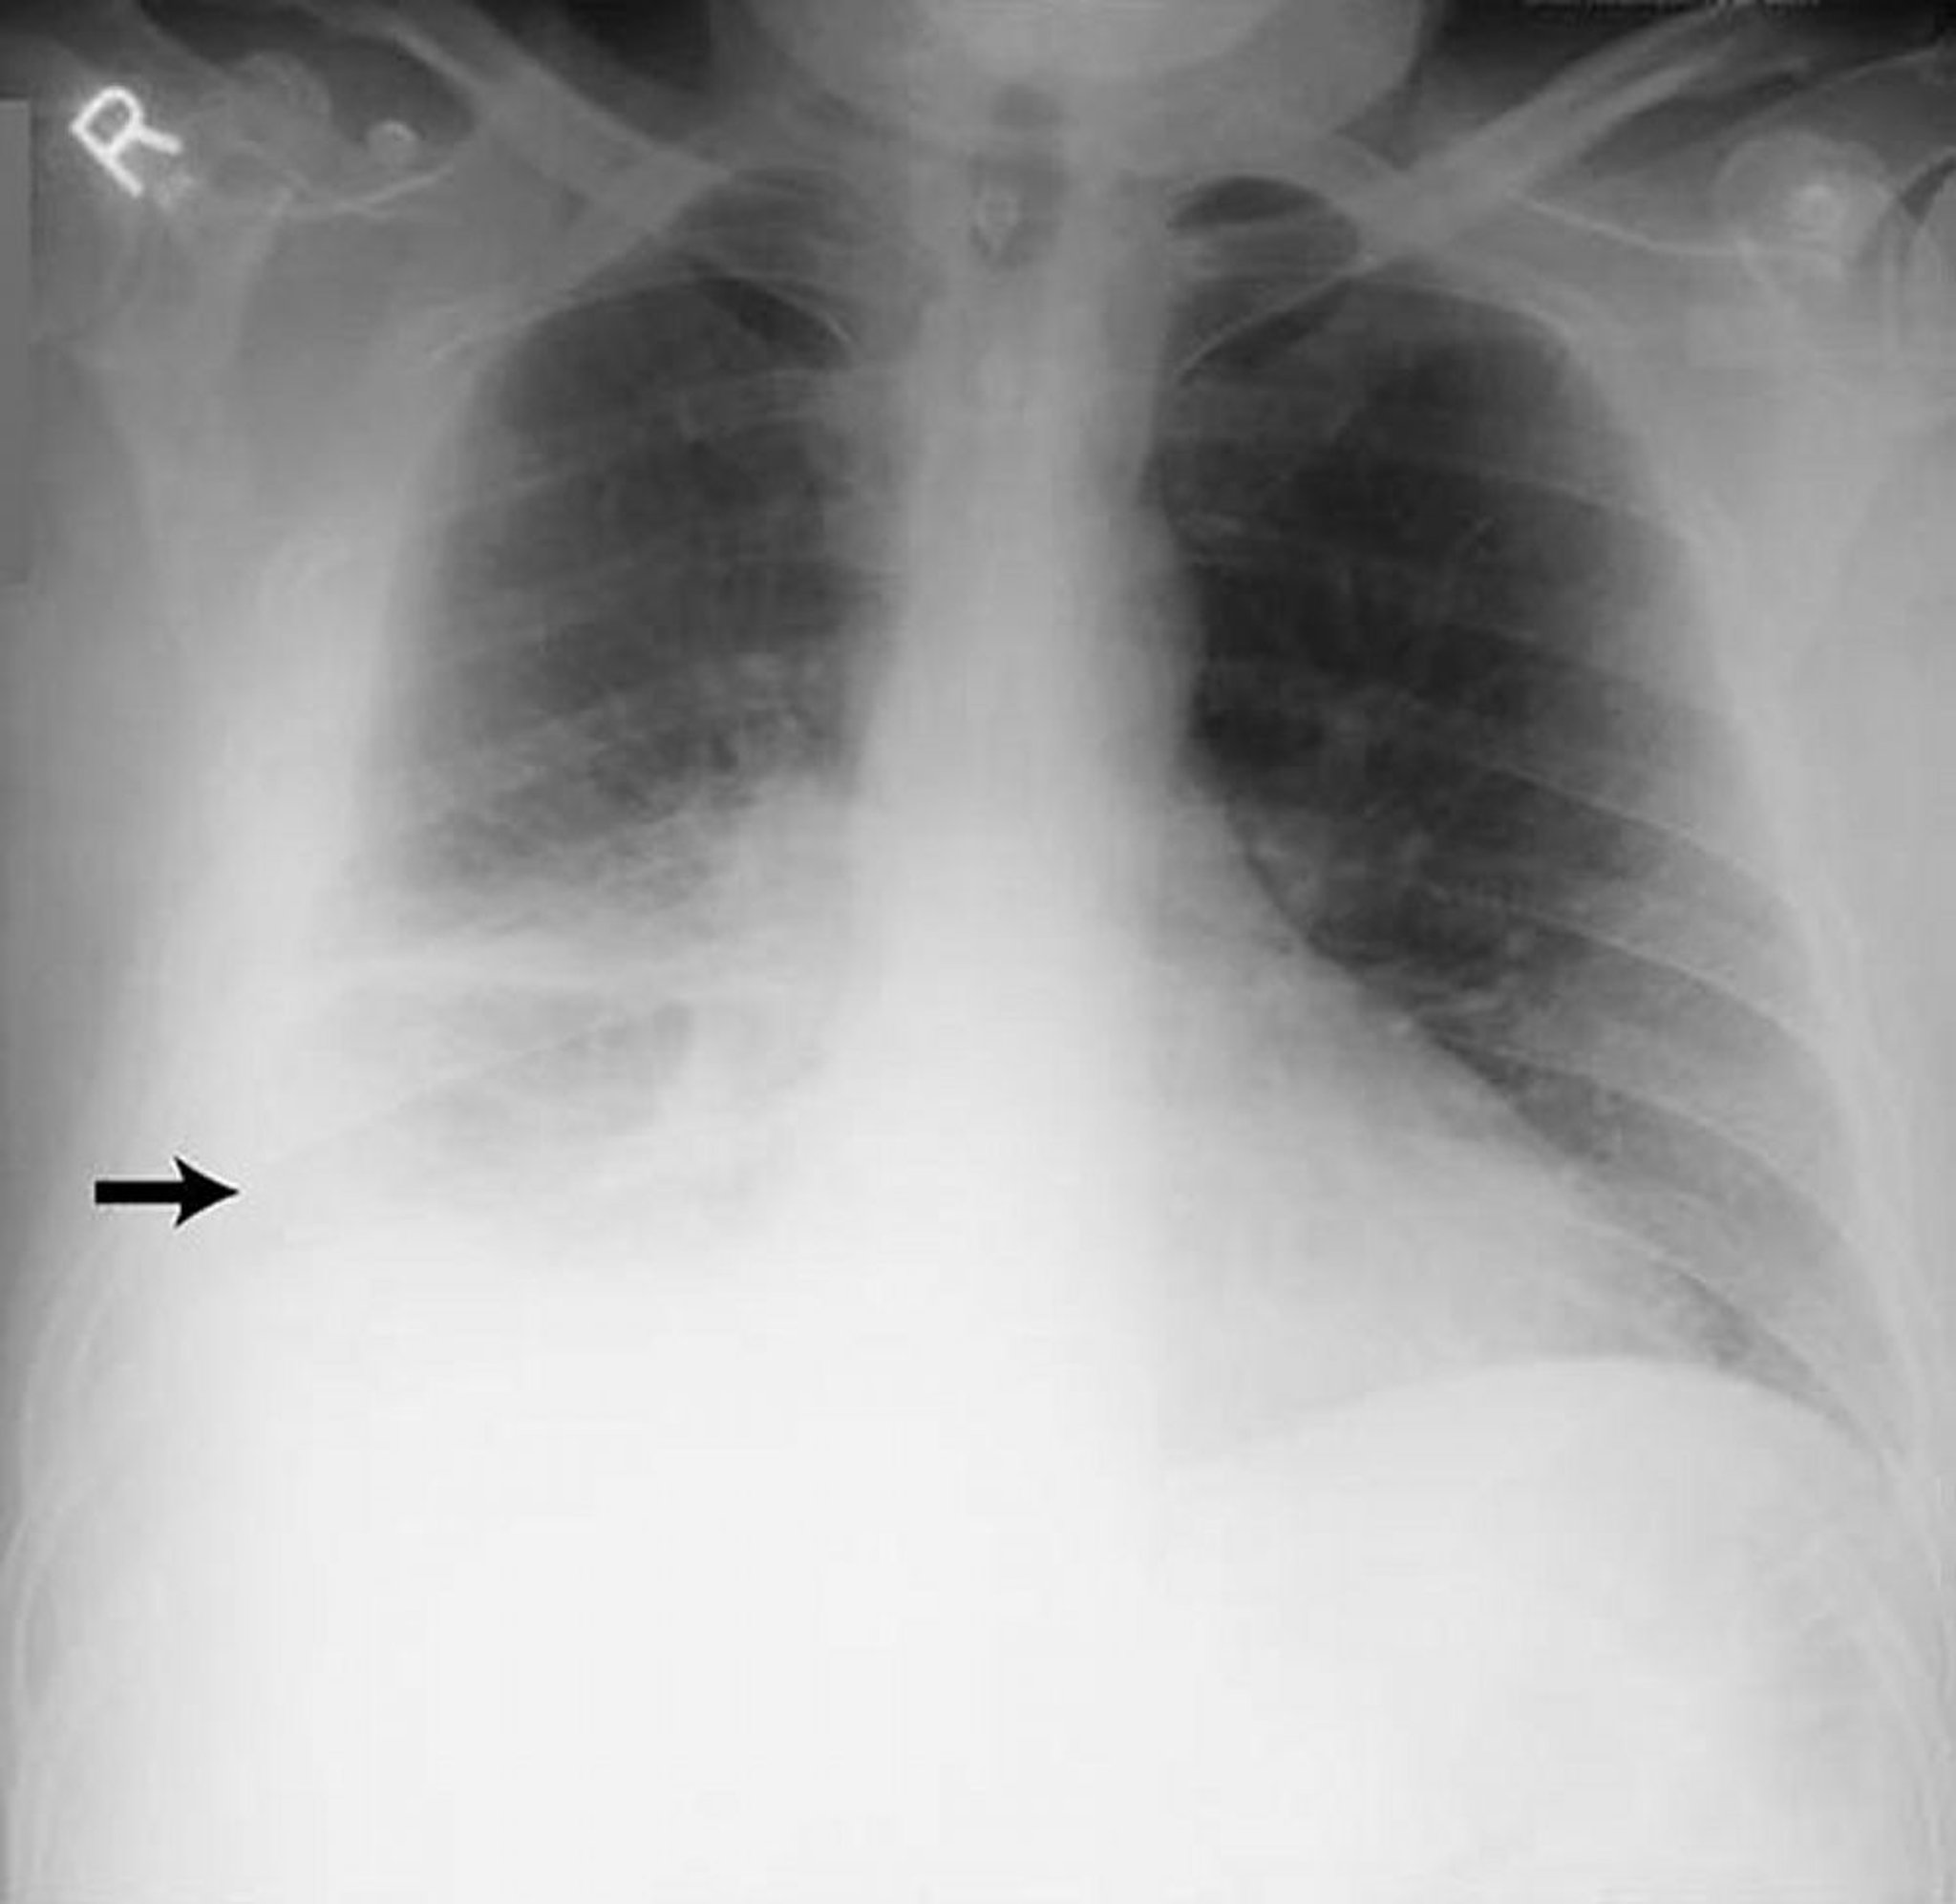

Versamento pleurico, grande

Esteso versamento pleurico destro (freccia) in un paziente con pleurite reumatoide.

By permission of the publisher. From Huggins J, Sahn S. In Bone's Atlas of Pulmonary and Critical Care Medicine. Edited by J Crapo. Philadelphia, Current Medicine, 2005.